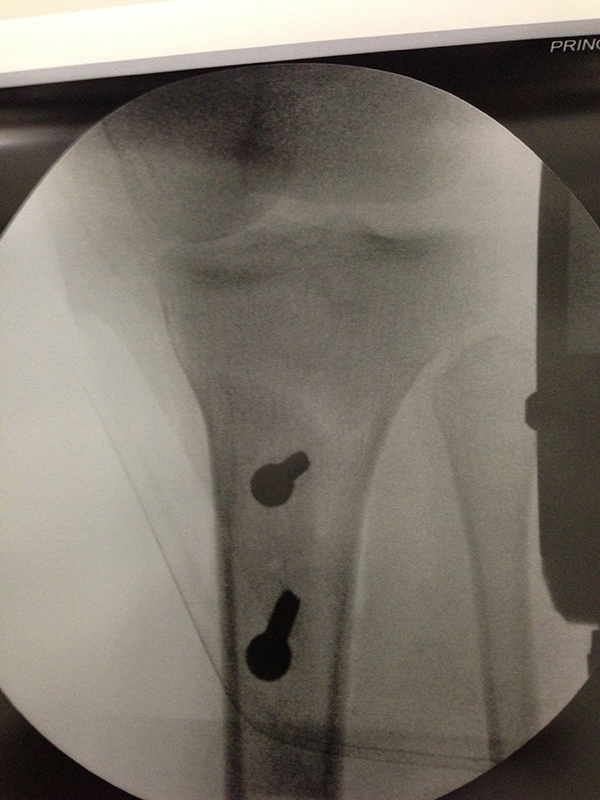

Bicondylar TIB Plateau Fracture

ACL Femoral Tunnel Drill

-

ACL Tibial JIG

ACL Tunnels Passing Graft

Tibial Tubercle Osteotomy